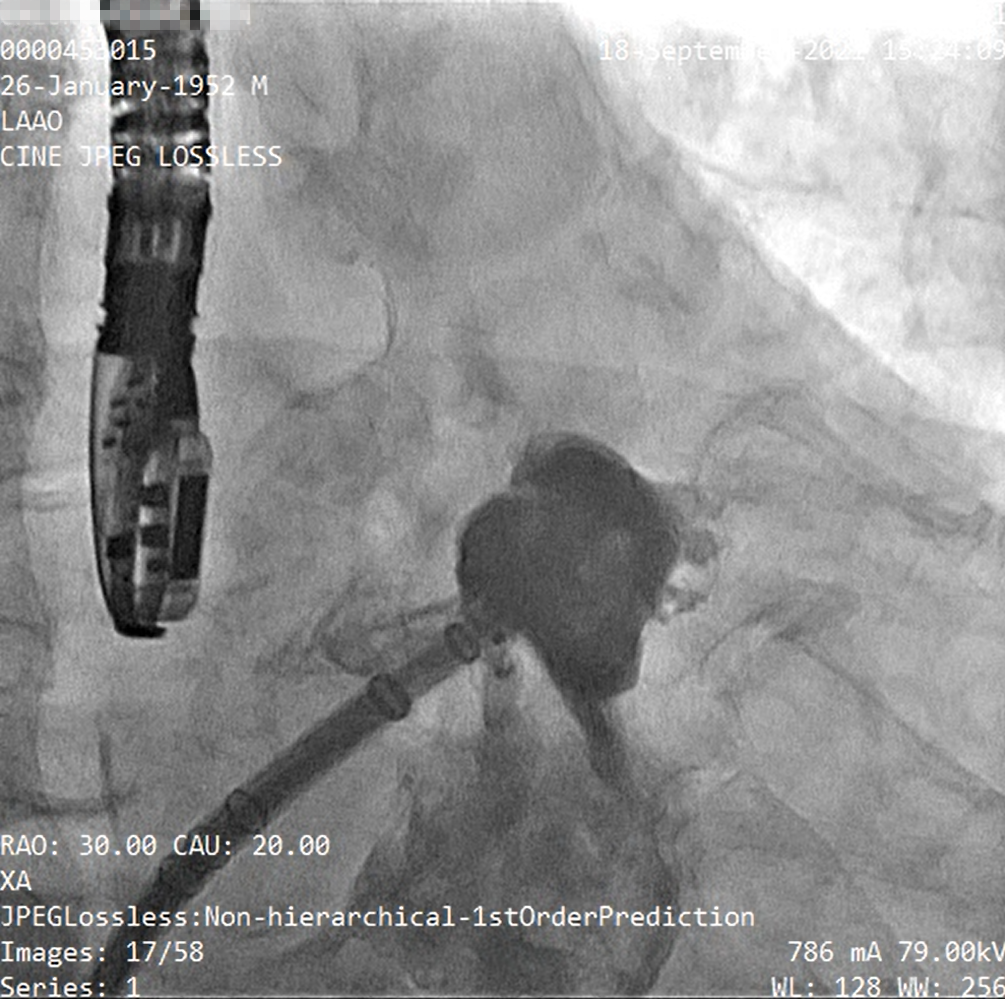

2021年9月18日成功置入澳门特别行政区首例WATCHMAN FLX左心耳封堵器

释放左心耳封堵器呈〝FLX BALL〞

经造影及食道超声检查后释放WATCHMAN FLX左心耳封堵器